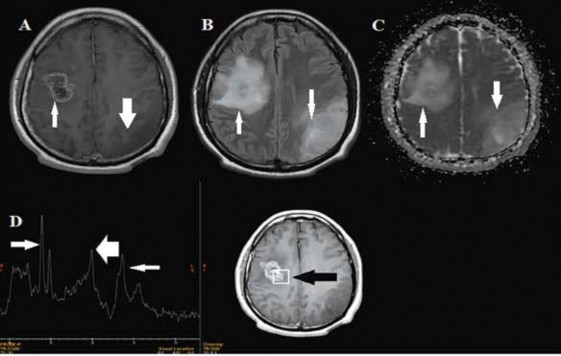

Sigue controles por consulta externa con manejo multidisciplinario; se le realiza RMN cerebral contrastada control a los 8 meses posoperatorios donde en la T1 contrastada se observa una lesión parietooccipital izquierda con ligera disminución de tamaño y lesión frontal derecha con captación de contraste en la periferia e hipointensidad en el centro, con supresión leve en FLAIR y en difusión, con pico de colina en la espectroscopia, pero con persistencia de la enfermedad aparentemente estable (Figura 3), por ello se decide continuar con quimioterapia adyuvante a dosis de 250 mg/día por 5 días/mes.